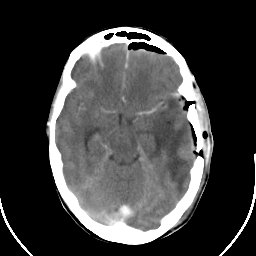

Metastatic bronchogenic carcinoma: Roentgen-ray CT (post-op) -- Slice #8

[Home][Help][Clinical] Slice 8